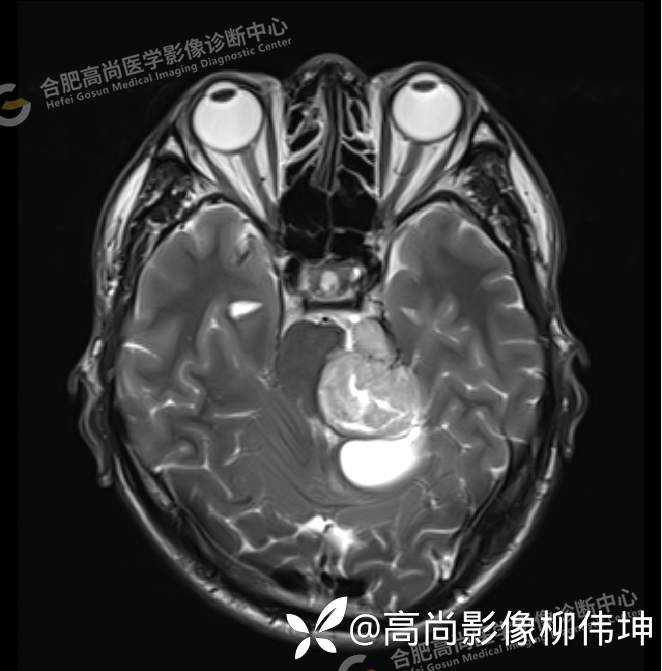

T2WI-tra

颅脑MRI平扫+增强示:双侧大脑半球对称,左侧桥小脑角区可见一团块状异常信号影,边界尚清,病灶与小脑幕宽基底附着呈“D”字征,上缘指状伸入幕缘上生长,病灶大小约43mmx42mmx36mm,其内信号不均,T1WI呈等低信号,T2WI呈混杂等高信号;FLAIR呈高信号,内可见条状低信号影,DWI呈稍高信号,ADC呈低信号,弥散轻度受限,病灶后方左侧小脑半球区可见一大小约33mmx16mm的弧形长T1长T2信号影,FLAIR呈低信号,其周围可见片状高信号影,相邻桥小脑角增宽。脑桥、小脑蚓部,小脑半球、第四脑室、环池受压变形,向右侧偏移,四脑室明显变窄,增强扫描病灶可见不均匀明显强化,邻近脑膜可见线样强化改变。其后方囊性灶未见异常强化。邻近骨质未见明显异常信号。左侧内听道显示正常;左侧中耳乳突内可见不规则性长T1长T2信号影。余脑实质内未见局灶性信号异常。双侧侧脑室及第三脑室体积增大,中线结构居中。矢状面示垂体形态大小正常,未见局灶性异常信号。

1.左侧桥小脑角区占位伴周围囊变,轻度梗阻性脑积水;考虑左小脑幕脑膜瘤。